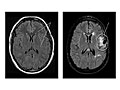

La resonancia magnética es una prueba que utiliza un campo magnético e impulsos de energía de ondas de radio para tomar imágenes de la cabeza. En muchos casos, la resonancia magnética proporciona información que no puede verse en una radiografía, una ecografía ni una tomografía computarizada.

Para una resonancia magnética de la cabeza, usted se tumba con la cabeza dentro de una máquina especial (escáner) que tiene un potente imán. La resonancia magnética puede mostrar daños en los tejidos o enfermedades, como infecciones o inflamaciones, o bien un tumor, un ataque cerebral o convulsiones. La información de una resonancia magnética puede guardarse y almacenarse en una computadora para estudiarla más a fondo. También pueden hacerse fotografías o placas de determinadas vistas.

En algunos casos, puede utilizarse un tinte (material de contraste) durante la resonancia magnética para mostrar imágenes de las estructuras con mayor claridad. El tinte puede ayudar a mostrar la irrigación sanguínea, detectar algunos tipos de tumores y mostrar zonas de inflamación.